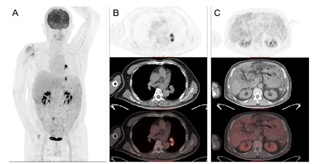

患者,男性,54岁,入院前10天无诱因出现腹胀,呈进行性加重,无法自行缓解。入院前2天行胸腹增强CT示:两肺多发实性结节,纵膈及食管下段多发肿大淋巴结,腹膜、网膜、肠系膜弥漫性增厚并多发软组织低密度影,腹盆腔积液(图1)。胃镜检查未见肿瘤病灶。入我科前1小时,出现胸闷、气促。2017年8月于外院行腰背部黑痣切除术,当时病理结果回报"皮内痣",家族中无类似病史。

PET-CT(图3):腹膜弥漫性增厚、代谢增高,纵膈多发高代谢灶,考虑恶性肿瘤;腰背部浅表及胃肠道未见高代谢病灶。